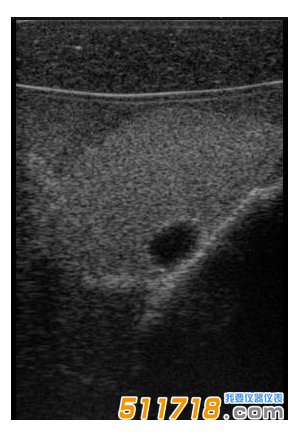

CIRS 074甲狀腺超聲訓(xùn)練模體包含一個(gè)略微擴(kuò)大的甲狀腺,位于一個(gè)擬人化的頸部。下巴和鎖骨被提供作為外部解剖標(biāo)志。體模提供氣管,頸內(nèi)靜脈和頸總動(dòng)脈作為內(nèi)部解剖標(biāo)志。每個(gè)甲狀腺葉包含一個(gè)囊腫和一個(gè)等回聲僵硬病變。可以在甲狀腺內(nèi)定制生產(chǎn)各種結(jié)節(jié)。*有材料都配制成超現(xiàn)實(shí)的。

可以對(duì)每個(gè)囊腫進(jìn)行細(xì)針抽吸。每個(gè)僵硬病變都設(shè)計(jì)用于超聲彈性成像的可視化,并且可以進(jìn)行活組織檢查。這些病變對(duì)甲狀腺是等回聲的并且具有標(biāo)準(zhǔn)的B模式成像。

單純囊腫